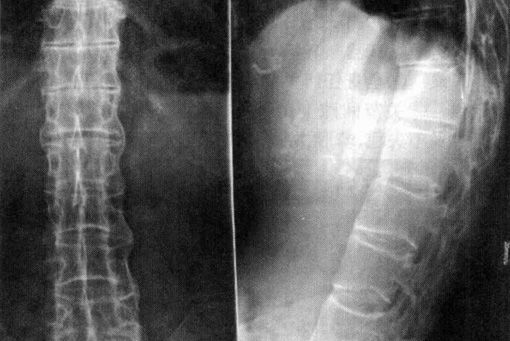

强直性脊柱炎

QZ16030094 姓名:陈先生 性别:男 年龄:32岁

- 病情

AS ①晚期 ②重度 病史:5年+

- 治疗

治疗后骶髂关节疼痛消失,腰椎前屈、背伸侧弯活动自如,膝关节无压痛感,复查血沉、C反应蛋白、等各项检查均已达到临床康复的标准。